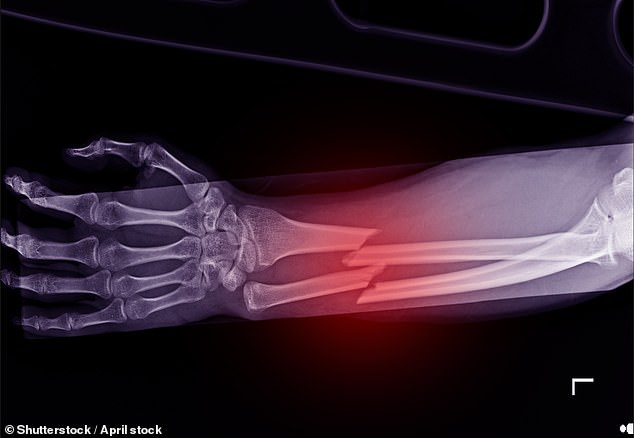

Osteoporosis – suffered by 3.5 million people in the UK – causes bones in the body to lose strength and break more easily.

The condition can be devastatingly painful, cause permanent disabilities and reduce patients’ independence, causing 500,000 broken bones every year in the UK.